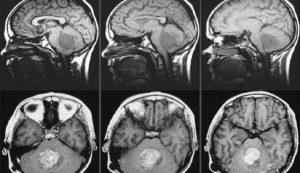

Atipik teratoid / rabdoid tümör (AT/RT) veya medulloblastoma gibi agresif beyin tümörleri geliştirmiş olan çocuklar için yeni bir umut kapısı